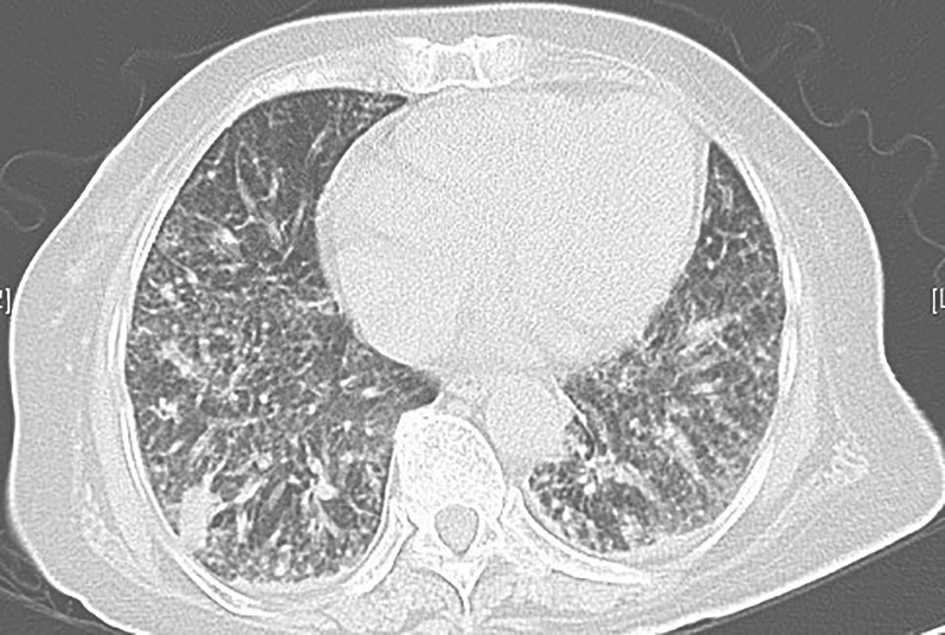

明确诊断后,予两性霉素B脂质体并逐渐加量至60mg/d[1mg/(kg•d)],联合伊曲康唑200mg (每天1次)静脉滴注,21天后改为口服伊曲康唑200mg(每天2次)抗真菌治疗4个月。患者体温逐渐下降,复查胸部CT较前明显好转(图12~图15)。到2013年8月为止,患者气促症状较前改善,复查胸部CT提示:双肺间质性病变较前明显好转,空洞样改变较前明显吸收。

图12治疗半个月后复查胸部CT表现

胸部CT示双肺弥漫病变较前吸收

图13治疗1个月后复查胸部CT表现

胸部CT示双肺病变继续吸收,空洞样改变有所吸收

图14治疗3个月后复查胸部CT表现

胸部CT示双肺病变基本吸收,空洞样改变遗留少许纤维条索和结节

图15治疗5个月后复查胸部CT表现

胸部CT示双肺病变及空洞基本吸收,遗留少许条索状纤维影